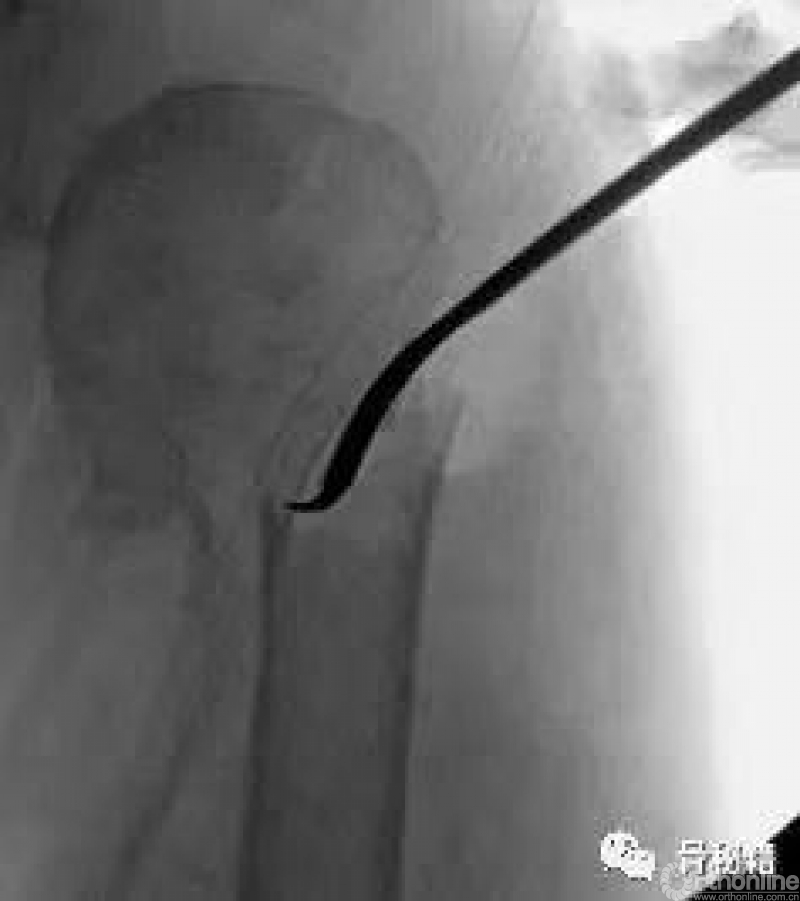

在复位好的基础上,植入合适的主钉导针

导针一旦植入,这个手术就完成了一半了

剩下就按照步骤进行